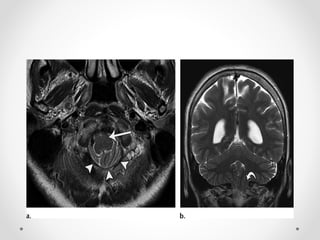

2.3 Thoát vị qua lều hướng lên

Do phần trên tiểu não thoát vị qua lều tiểu não lên trên

Nguyên nhân:

- Do hiệu ứng khối vùng hố sau

- Do giảm đột ngột áp lực nội sọ trên lều

Hậu quả:

- Chèn ép ĐM não sau và ĐM tiểu não trên

- Ứ nước não thất do chèn cống Sylvius

CĐHA:

HA trực tiếp: phần trên tiểu não qua lỗ lều tiểu não lên

trên

- Đè đẩy phía sau cuống não di lệch và xoay cuống

não

- Hình thái "Spinning top" của cuống não

HA gián tiếp:

- Xoá bể củ não sinh tư

- Nhồi máu theo vùng cấp máu ĐM tiểu não trên và ĐM

não sau

2.3 Thoát vịqua lều hướng lên Do phần trên tiểu não thoát vị qua lều tiểu não lên trên Nguyên nhân: - Do hiệu ứng khối vùng hố sau - Do giảm đột ngột áp lực nội sọ trên lều Hậu quả: - Chèn ép ĐM não sau và ĐM tiểu não trên - Ứ nước não thất do chèn cống Sylvius

2.3 Thoát vịqua lều hướng lên CĐHA: HA trực tiếp: phần trên tiểu não qua lỗ lều tiểu não lên trên - Đè đẩy phía sau cuống não di lệch và xoay cuống não - Hình thái "Spinning top" của cuống não HA gián tiếp: - Xoá bể củ não sinh tư - Ứ nước não thất do chèn cống Sylvius - Nhồi máu theo vùng cấp máu ĐM tiểu não trên và ĐM não sau